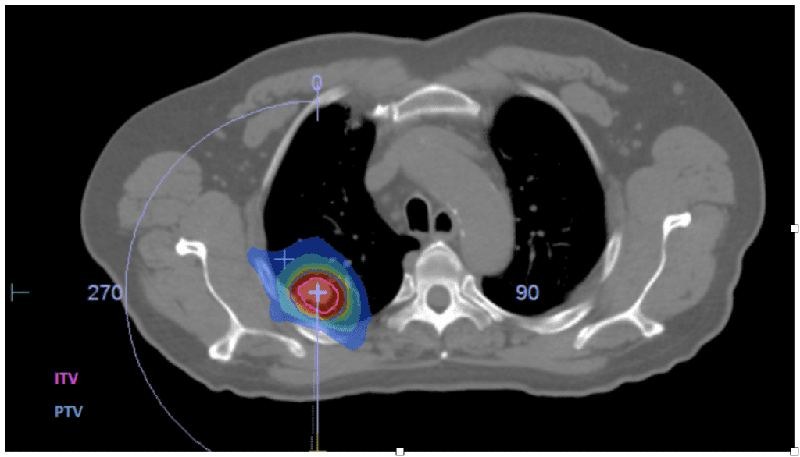

La radiothérapie stéréotaxique (SBRT — Stereotactic Body Radiation Therapy) est une technique de pointe qui délivre des doses très élevées de rayonnement en un petit nombre de séances (3 à 5), avec une précision sub-millimétrique. Elle utilise de multiples faisceaux convergeant sur la tumeur depuis différents angles, concentrant l'énergie sur la cible tout en préservant les tissus sains.